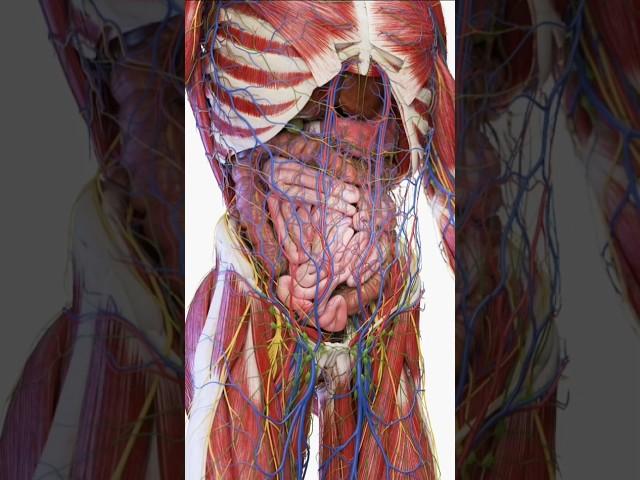

Top five fact about human body #facts #factoftheday #facts #didyouknow #trending #ytshorts #viral